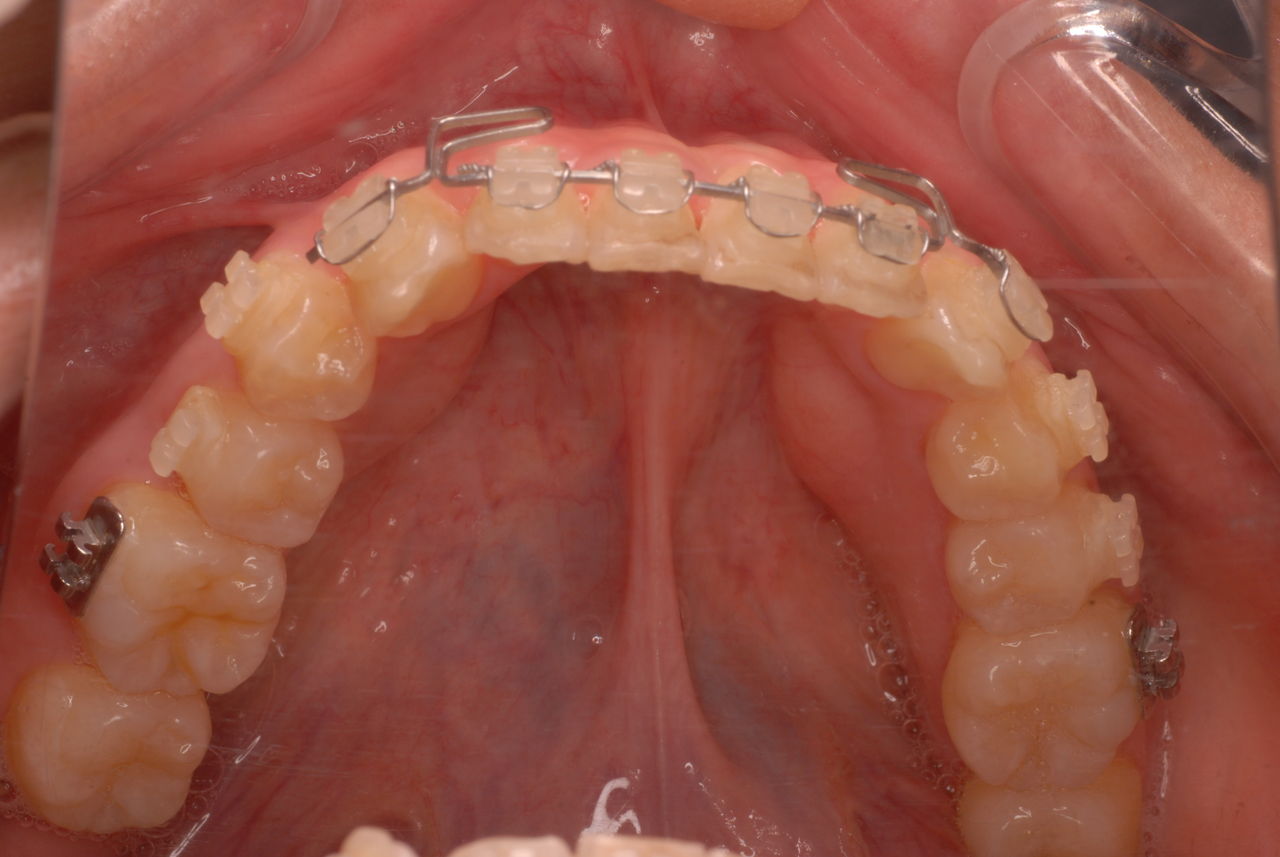

歯を削らないといいましても結局歯の間を削りスペースを確保したそうですから、何らかの歯に対する傷害はしているのです。それは虫歯や歯周病を起こしやすい理由にもなりますからこれからも要注意なのです。二年間という貴重な時間を費やしていますから患者本人は大変だったと思います。そして二年間を要したならば更に二年間動かないようにするための入れ歯やマウスピースを装着し続けなければいけないのです。

綺麗になりたいのはわかりますが、注意しなければならないことも多いのです。矯正専門医というのは歯学部を出ていますが、歯を動かすテクニックはあるのでしょうが、虫歯や歯周病の治療、そして一般歯科の経験がないので噛合せがおかしくなってもあまりわからないことが多いのです。理解していて注意深く治療するかたもいるようですが、大半は“素人”と考えて良いのです。やはり矯正も一般歯科もやられている歯科医のほうが私は対応出来ると考えています。